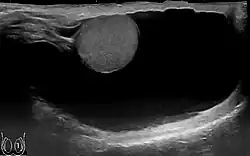

Scrotal ultrasound of a 10 cm large hydrocele, with anechoic (dark) fluid surrounding the testicle

The swelling is soft and non-tender, large in size on examination, and the testis cannot usually be felt. The presence of fluid is demonstrated by transillumination. These hydroceles can reach a huge size, containing large amount of fluid, as these are painless and are often ignored. They are otherwise asymptomatic, other than size and weight, causing inconvenience. However the long continued presence of large hydroceles causes atrophy of testis due to compression or by obstructing blood supply. In most cases, the hydrocele, when diagnosed early during complete physical examination, are small and the testis can easily be palpated within a lax hydrocele. However Ultrasound imaging is necessary to visualize the testis if the hydrocele sac is dense to reveal the primary abnormality. But these can become large in cases when left unattended. Hydroceles are usually painless, as are testicular tumors. A common method of diagnosing a hydrocele is by attempting to shine a strong light (transillumination) through the enlarged scrotum. A hydrocele will usually pass light, while a tumor will not (except in the case of a malignancy with reactive hydrocele).

The accuracy of the diagnosis must be ascertained. Great care must be taken to differentiate a hydrocele from a scrotal hernia or tumor of the testicle. Ultrasound imaging can be very useful in these cases. A hernia usually can be reduced, transmits a cough impulse, and is not translucent. A hydrocele cannot be reduced into the inguinal canal and gives no impulse on coughing unless a hernia is also present. In young children a hydrocele is often associated with a complete congenital type of hernial sac.